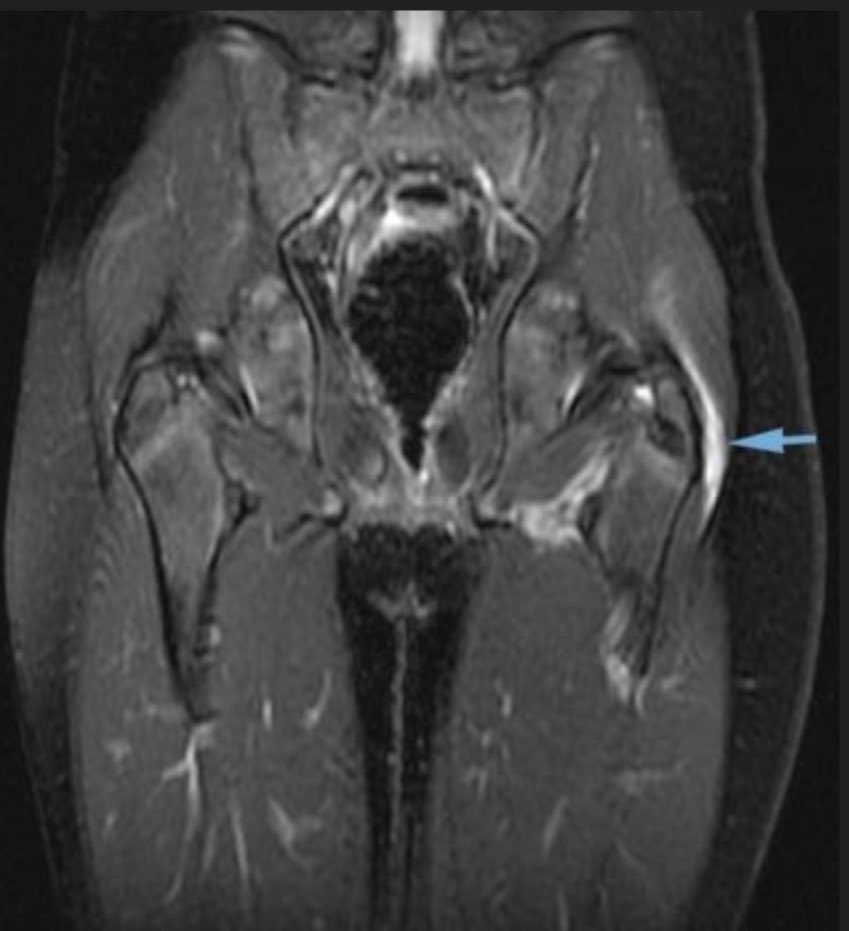

عادة ما تكون الأشعة السينية x ray سليمة، ولكن قد تظهر علامات هذا الالتهاب بالرنين المغناطيسي-السهم الأزرق-، والأشعة الصوتية.